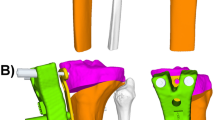

Using a 3D printer (Objet 24, Stratasys Inc., Rehovot, Israel), four square column models, each with a 10° posterior slope, were produced. The four SPOI types were produced using jigs with different angles, which are required to attach the square column model to a testing machine (Fig. 2). The axis of coronal correction or rotation acts as a lateral hinge in medial open-wedge HTO. In the simulation using the testing machine, the axis of coronal correction or rotation was also a lateral hinge. The rotation of the square column model occurred around the lateral hinge. The central axis of the jig was the lateral hinge. Therefore, the sagittal plane angle of the jig was the SPOI.

a Four square column models with jigs attached at different angles. b After correction with the MTS 858 Bionix machine (MTS System Corp), the end-point of the posterior slope was measured using a MicroScribe™ system (Revware Systems, Inc.). c The change in posterior slope was determined using Rhinoceros® software (McNeel)

The correction angle was increased at 5° intervals from 0° to 30° using a testing machine (MTS 858 Bionix; MTS System Corp., Eden Prairie, MN, USA) (Fig. 2). The change in posterior slope was measured 10 times using the MicroScribe™ system (Revware Systems, Inc., Raleigh, NC, USA). The reported accuracy of the device was ±0.05 mm [14]. To measure the change in posterior slope with the MicroScribe™ system, two holes were made in advance in the square column model. The anterior end-point of the posterior slope was point A and the posterior end-point of the posterior slope was point B (Fig. 2). These two points were reconstructed with a slope line using Rhinoceros® software. Using this software, the change in posterior slope was determined as the angle (Fig. 2).